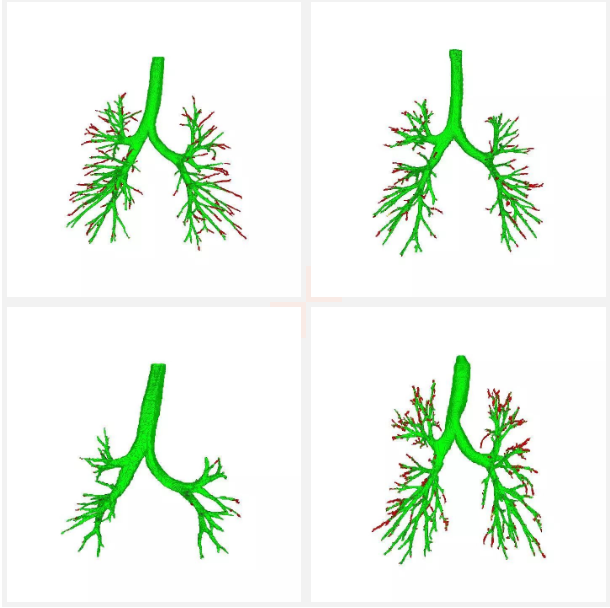

以上是本模型在exact09比賽中的部分提取結果,綠色表示跟醫生手工標注的吻合的部分,紅色表示比醫生手工多檢測出來的部分,通過對比可以看出,本模型相比手工提取,具有更高的敏感性,能檢測出非常細小的氣管。